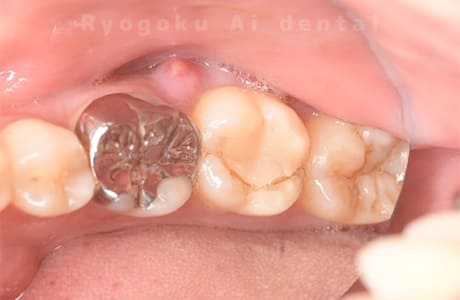

Case10

-

- 原因

- 右下6番 重度カリエス

- 治療内容

- 右下8を右下6へ移植に自家歯牙移植

- 治療期間

- 約1か月半

- 治療費用

- 220,000円

右下の銀歯が外れかかっているとのことでご来院された患者様です。虫歯が大きく、かつ歯が割れており、保存不可能と判断し、親知らずの移植を行いました。

<リスク・副作用>

治療後、痛みや違和感、出血、腫れなどが出る事があります。喫煙者、糖尿病などの方の場合、歯が生着しない場合があります。